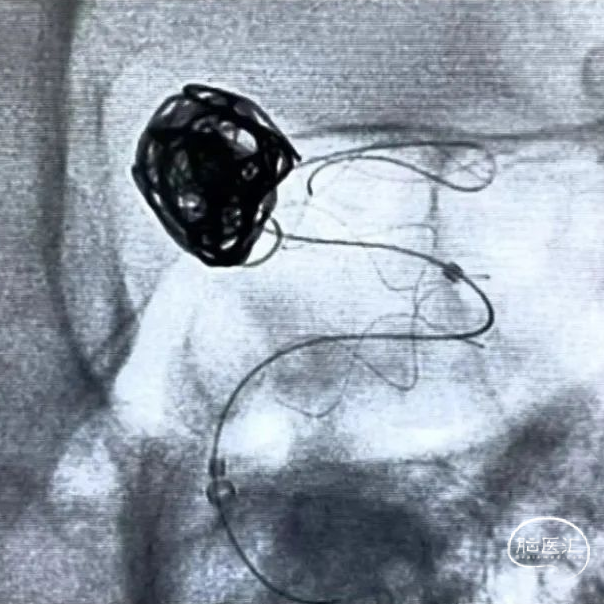

经弹簧圈微导管向瘤腔内填入12mm*40mm弹簧圈。

释放支架:

选用4.5mm*45mm Tubridge血流导向密网支架在远端预打开再回撤定位,缓慢推出支架进行头端锚定,支架头端位于大脑中动脉主干,造影观察后,继续缓慢释放Tubridge血流导向密网支架至瘤颈中段。确保支架充分贴壁,继续缓慢释放Tubridge血流导向密网支架,直至支架完全释放。

栓塞动脉瘤:

继续经弹簧圈微导管填入6mm*20cm、5mm*15cm弹簧圈。

微导丝支架尾端按摩,使支架充分贴壁。

术后即刻影像,造影示动脉瘤腔内空虚处滞留明显,载瘤动脉通畅。遂撤出弹簧圈微导管,支架输送系统。